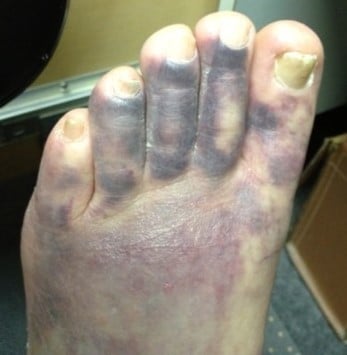

Despite a wide differential diagnosis, one of the most common cause for a blue or black toe is athero-embolism. Atheroembolic lesions are characteristically painful, at least at first. Sudden onset is a clue to embolism, as an embolism occurs suddenly. The lesions may evolve over time or not, but without treating the source, embolic lesions tend to be harbingers of more lesions.

Emboli from atherosclerotic plaque are one of the most common cause of blue toes. Emboli that can obstruct blood vessels of the toes and cause blue toe syndrome most commonly arise in the heart (in the left ventricle) or in the aorta. In fact, most emboli arise in the arteries between the infra-renal aorta and the popliteal artery. Practically, unilateral blue toes should prompt a search for a popliteal artery aneurysm, iliac artery aneurysm or aortic aneurysm.

It is known that an aortic atherosclerotic plaque is more prone to dislodge or be clinically significant if it is more than 4 mm thick or if it contains mobile elements. In one study the prevalence of aortic plaques was over 43% and complex plaques were present in 7.6%. These figures make aortic plaques as common a cause of stroke as carotid plaques and atrial fibrillation. A complex, mobile aortic plaque carries an annual risk of over 10% for embolization. The vascular bed to which the plaque embolizes is dependent on the location of the plaque. However the combination of stroke and blue toe syndrome is common.